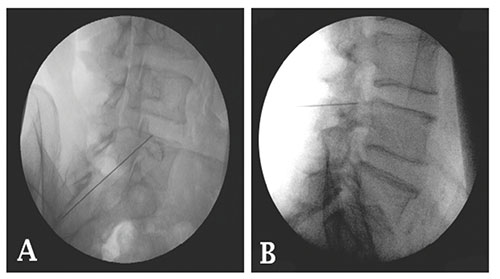

Tanto o bloqueio quanto a injeção intraarticular facetária podem ser realizadas através do uso da radioscopia (figura 4 e figura 5) ou do ultra-som.

Figura 4: A- Vista radiográfica obliqua do ponto do bloqueio do ramo medial. B- Vista radiográfica lateral do ponto do bloqueio do ramo medial.